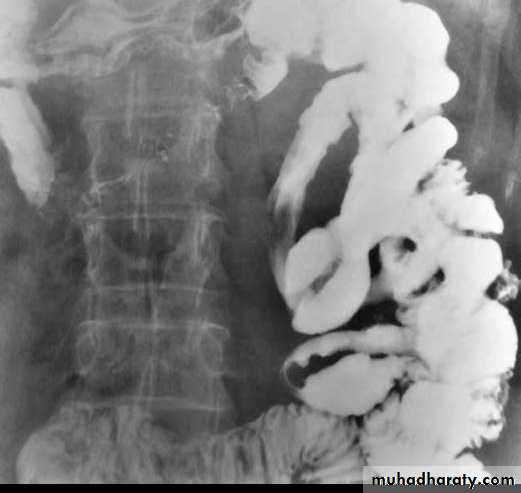

c. Due to bowel wall thickening, the folds may be thickened, distorted or disappear & the loops may be separated in severe wall thickening. With inflammatory mass, greater displacement of loops is seen.Mucosal fold thickening, ulceration, nodularity, asymmetric bowel wall

involvement, regions of narrowing, and separation of small bowel loops are present.d. Fistulae to the other loops of SB, colon, bladder or vagina.